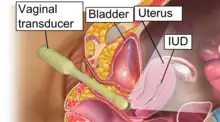

此檢查可以透過經腹部超音波進行,檢查前會讓受檢者喝水,讓膀胱充飽尿液,作為聲學窗(acoustic window),在檢查骨盆器官時,有更好的成像效果,也可以用經陰道超音波進行,會使用特製的陰道換能器。經陰道超音波影像會利用高頻的影像,對卵巢、子宫及子宮內膜的解析度較好(一般情形看不到輸卵管,只有在特別擴張的情形才看得到),不過影像穿透能力有限,較大,較靠近腹部的部份比較適合用經腹部超音波來檢查。在進行腹部超音波時,充飽尿液的膀胱的檢查也有幫助,因為超音波在其中比較不會衰減,比較可以檢查到在膀胱後面的卵巢、子宫。婦科超音波若是用經陰道超音波的方式進行,依定義來看是侵入性醫療。檢查會由超音波檢查師進行,或是受過超音波訓練的婦科醫師進行。